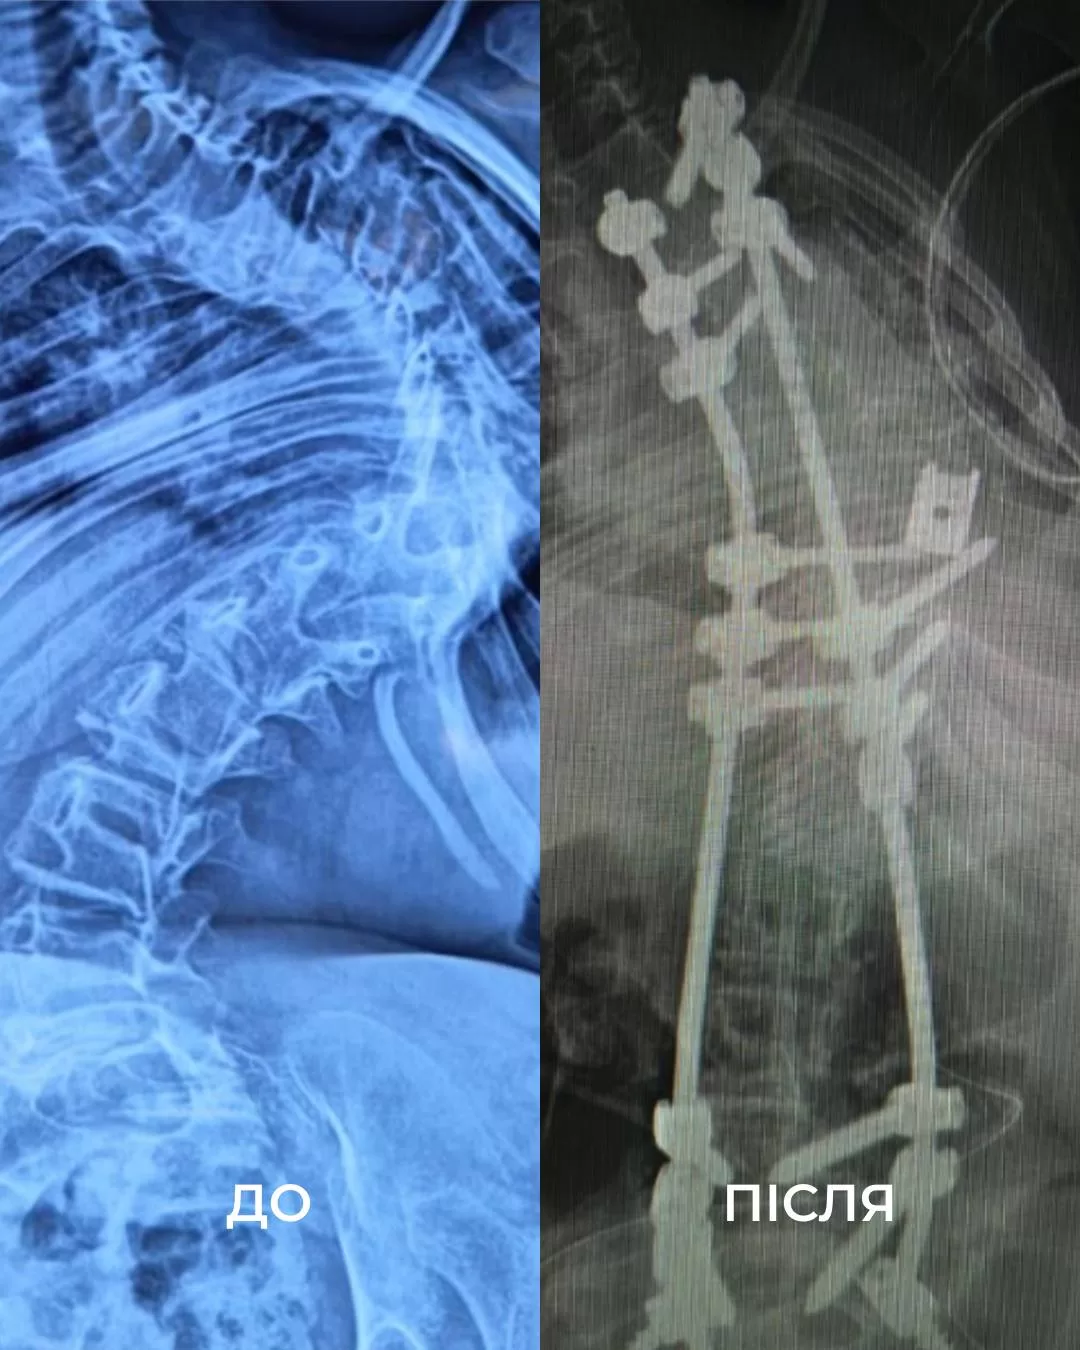

«Когда девочке было шесть месяцев, ее мама заметила, что позвоночник дочки изгибается полумесяцем. После генетического обследования у ребенка диагностировали редкое заболевание — миопатию Бетлема. Это заболевание характеризуется врожденно слабой мускулатурой, что со временем и приводит к тяжелому сколиозу. С годами состояние только ухудшалось: неутихающая боль, одышка, невозможность долго сидеть. Позвоночник ребенка искривился на 160 градусов. Дома девочка передвигалась с ходунками, в школе — на инвалидной коляске. Часто бывала в больницах и на реабилитации», — рассказали в больнице.

Виктория находилась под наркозом 18 часов, затем, из-за слабых мышц, еще две недели провела в реанимации под кислородом. Хирургам удалось выровнять позвоночник девочки на 85%.